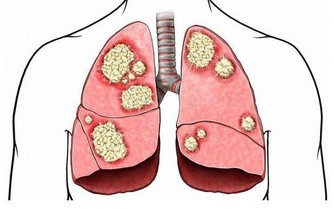

而繼發性腦瘤,是從其他部位(如乳房或肺部)擴散到大腦的癌性生長。

大部分腦腫瘤都屬於這種類型。

由於現在化療能夠延長人們的生命,使得癌症有更多的機會復發並轉移到大腦,

因此在過去的幾十年裡,繼發性腦瘤已經變得更加普遍。